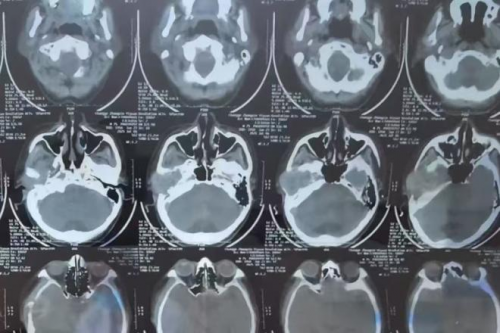

接诊张大爷的是国内知名耳鼻喉科专家娄卫华教授。娄教授详细询问病史后,为张大爷安排了CT影像和耳内窥镜检查。结果显示张大爷右侧颞骨附近存在显著肿物,根据影像学表现和症状判断为“右侧颞骨肿瘤”。娄教授建议尽快实施手术切除,以防病情进一步加重,同时明确病理性质。

由于颞骨区域紧邻多条重要神经和血管,手术难度较高,可能面临面瘫或听力丧失等并发症。娄卫华教授组织医疗团队进行了详细讨论,为张大爷设计了一套精准微创的手术方案,确保安全和效果双重达标。术前准备充分后,娄卫华教授亲自主刀完成了“右侧颞骨肿瘤切除术”。手术过程中,娄教授展现了丰富的临床经验和娴熟的技艺,成功完整切除了肿物,同时保护了周围的重要组织。整个手术过程顺利,出血量少,术后患者状态良好。